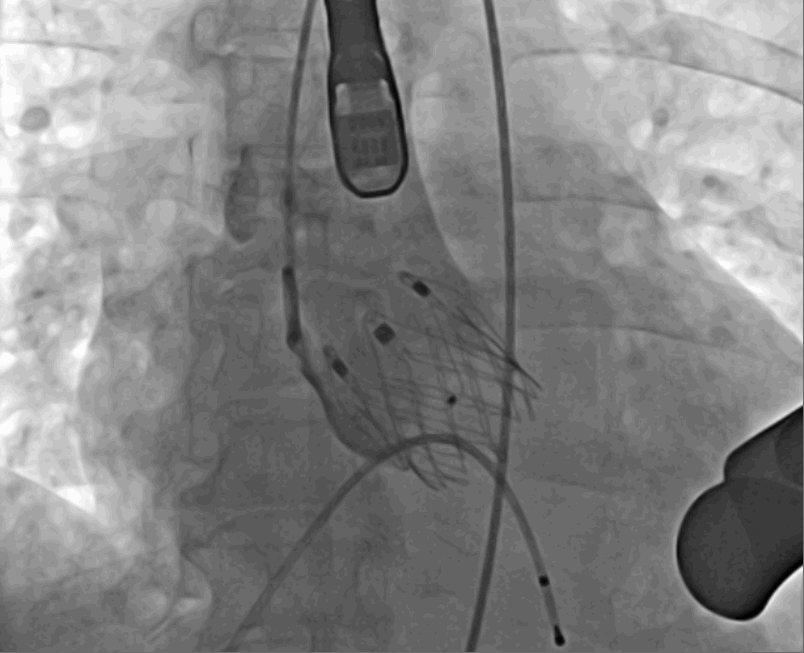

術(shù)前DSA影像圖